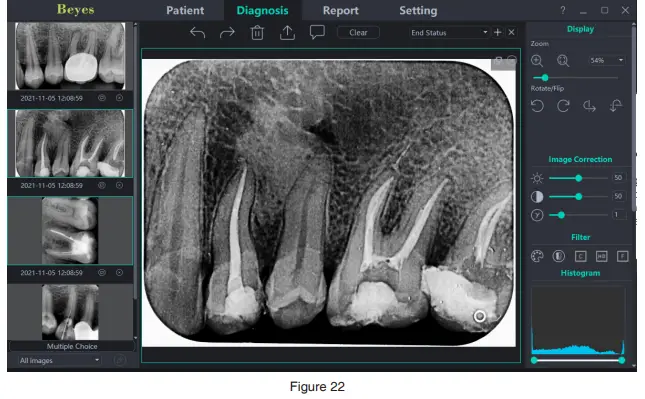

- Diagnostic module

Click the “Diagnosis” button to enter the diagnosis module.

Click the image on the left to select an image to be processed. There are image processing tools on the right side of the diagnosis interface, such as Display, Image Correction, Measuring, View, Enhance, Sharpening, Histogram, Annotation, etc. Select the image processing tool and adjust the image quality to a satisfactory level. In the Enhance, click the “HD” button and the image will be enhanced. Click the “HD” button again to cancel the enhancement.

Use image processing tools to adjust image quality. Click the “Add Temporary State” button to save the image quality at this time. Select the temporary state in the drop-down box to reproduce the image.

There are delete, export, and image information functions above the processed image. These functions are similar to the corresponding functions of the patient module. When multiple images are selected for processing, click the “Clear” button to close them all. Move the mouse wheel up and down to zoom in and out of the image. Hold down the right button and move the mouse up to increase contrast, move down to decrease contrast, move left to decrease brightness, and move right to increase brightness. Select an image, and click the linear measurement icon (or angle measurement icon) in the Measuring. Click the left mouse button to form the starting point and move the mouse. Click the left mouse button again to form the end point and right-click the

end point to end the measurement. The measurement line will be displayed on the image, and meanwhile the corresponding annotation of the measurement line will be displayed in the Annotation. As is shown in Figure 22: